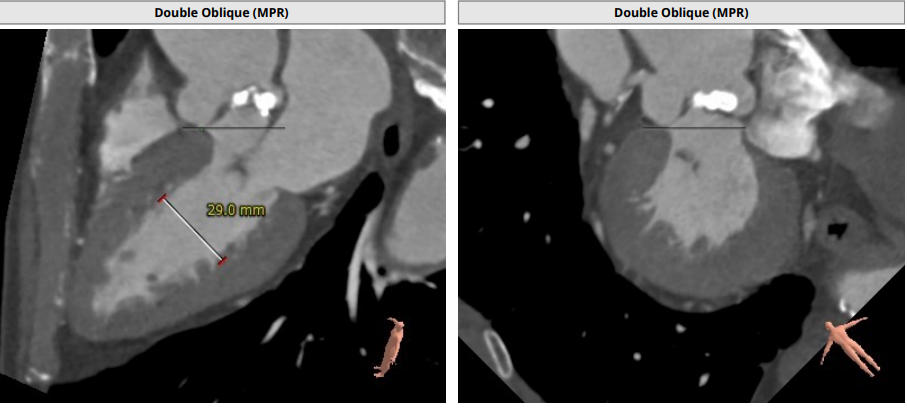

主动脉根部:

Annulus:23.3 mm,LVOT:21.9 mm,STJ:30.8 mm,Asc.AO:43.5 mm

LCA:13.2 mm,RCC:14.0 mm

瓣环及左室流出道呈开放式结构

TYPE1 二叶瓣,钙化集中无冠窦瓣叶侧

升主动脉增宽,最宽处为 47.1 mm(55.7 mm)

左右冠高度合适

心肌增厚,心室小

TYPE1 型二叶瓣,重度钙化,钙化呈单边分布,主要集中在无冠窦侧,左右可见非钙化脊,左冠高度约 13.2 mm,右冠高度约 14 mm,法式窦结构大,STJ 高度约 19.4 mm、直径约 30.8 mm,升主动脉可见增宽,最宽处约 47.1 mm,心脏角度约 46°,左室大小可,右窦居中体位:RAO4°、CAU21°,左冠切线位:LAO2°、CAU16°。